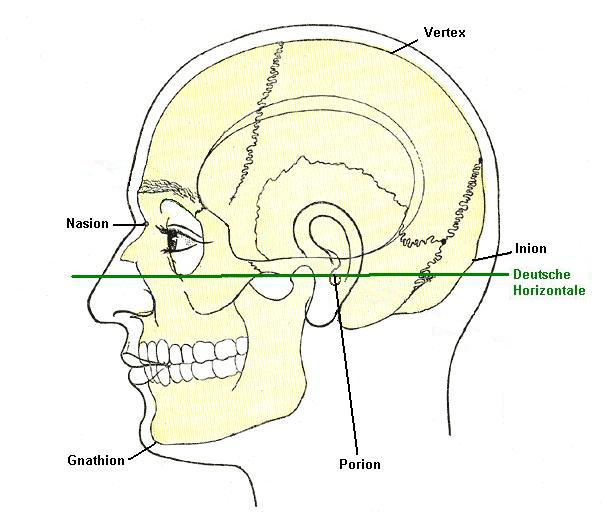

Positionen zur EEG Ableitung

|

|

|---|---|

|